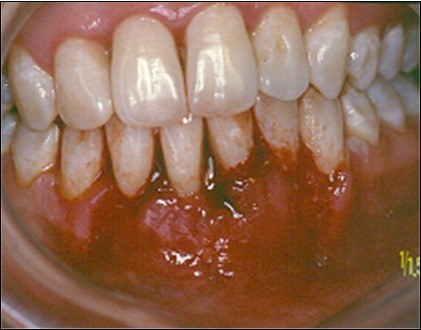

The patient under hard emotional stress that associated with bacterial plaque promoted ANUG with necrosis of alveolar bone and marginal gingival soft tissue in 31 and 41 (Figure 1). The patient was free of systemic disease and was not currently receiving any medication. Initial therapy was carried out using Er-YAG laser, to promote scaling and root planning and oral hygiene instruction. After initial therapy (Figure 2) the surgical method employed consists of the following steps as described by Langer and Langer5.